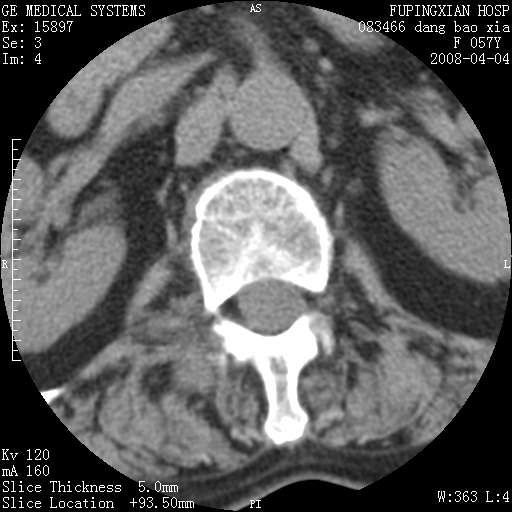

标题: CT12677:女性,57岁,疼痛数月。 [打印本页]

标题: CT12677:女性,57岁,疼痛数月。

椎体及附件骨质破坏同时伴软组织肿块,首先考虑恶性肿瘤。

骨组织起源,膨胀,软组织肿块=恶性改变:首选骨巨,其次转移瘤,再次脊索瘤

椎体及附件溶骨性破坏,周围巨大软组织肿块,首先考虑转移瘤。